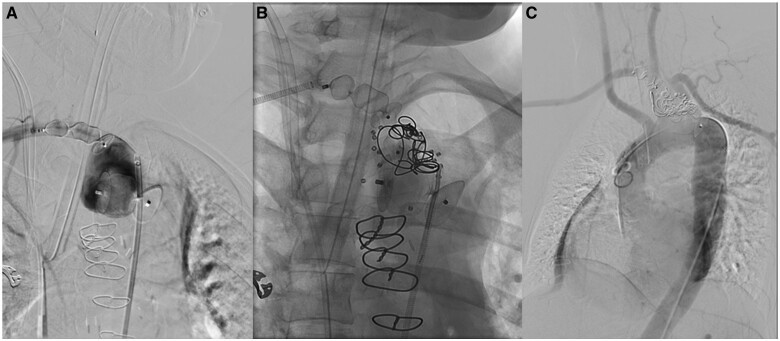

Aneurysms of an aberrant right subclavian artery (ARSA) are rare but constitute a potentially lethal condition, especially with concomitant Marfan syndrome (MFS). A 27-year-old female with confirmed MFS presented with a relevant progression of a known aneurysm of an ARSA in MRI. The patient had undergone valve-sparing aortic root replacement (David procedure) 4 months prior. After interdisciplinary discussion, she underwent endovascular exclusion of the aneurysm using a combination of established vascular plugs and novel shape memory polymer embolization plugs to fill the large ARSA aneurysm volume. The shape memory polymer embolization plugs expand in the vessel to a porous scaffold, designed to support thrombus formation throughout its structure. The polymer is also radiolucent, which minimizes artefact and facilitates follow-up imaging. Development of a strategy for the treatment of ARSA aneurysms is challenging and different surgical, endovascular, and combined approaches have been published. Interdisciplinary discussion is crucial to minimize the overall risk and trauma. In our case of a young female and new mother, an endovascular approach was successfully and safely performed. The future need for surgery due to concomitant MFS is expected.